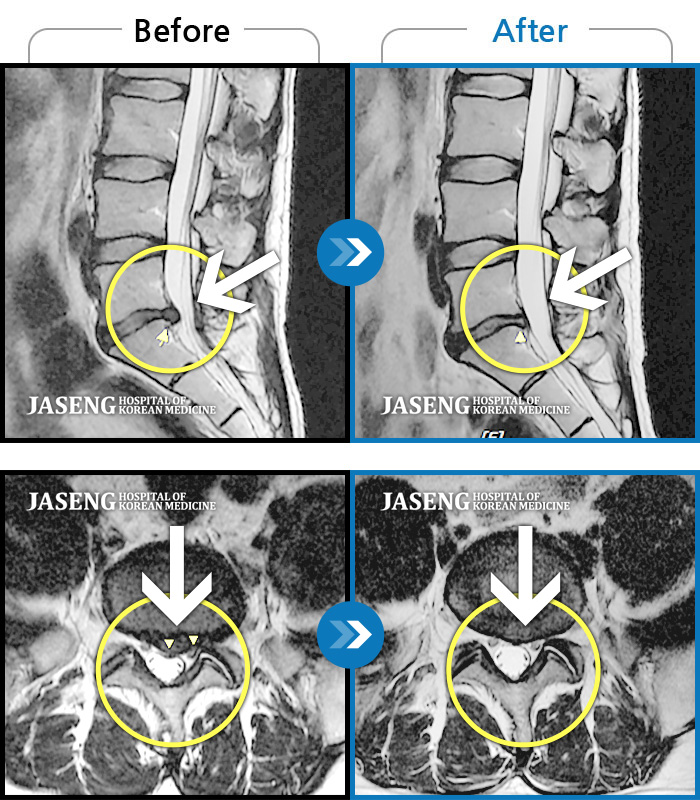

MRI를 통한 지금 허리 상태의 정확한 판단을 시작으로

MRI사진을 보면서 제 상태가 어떤건지 왜 아픈건지 앞으로 어떻게 해야하는지 친절히 잘 설명해주셔서